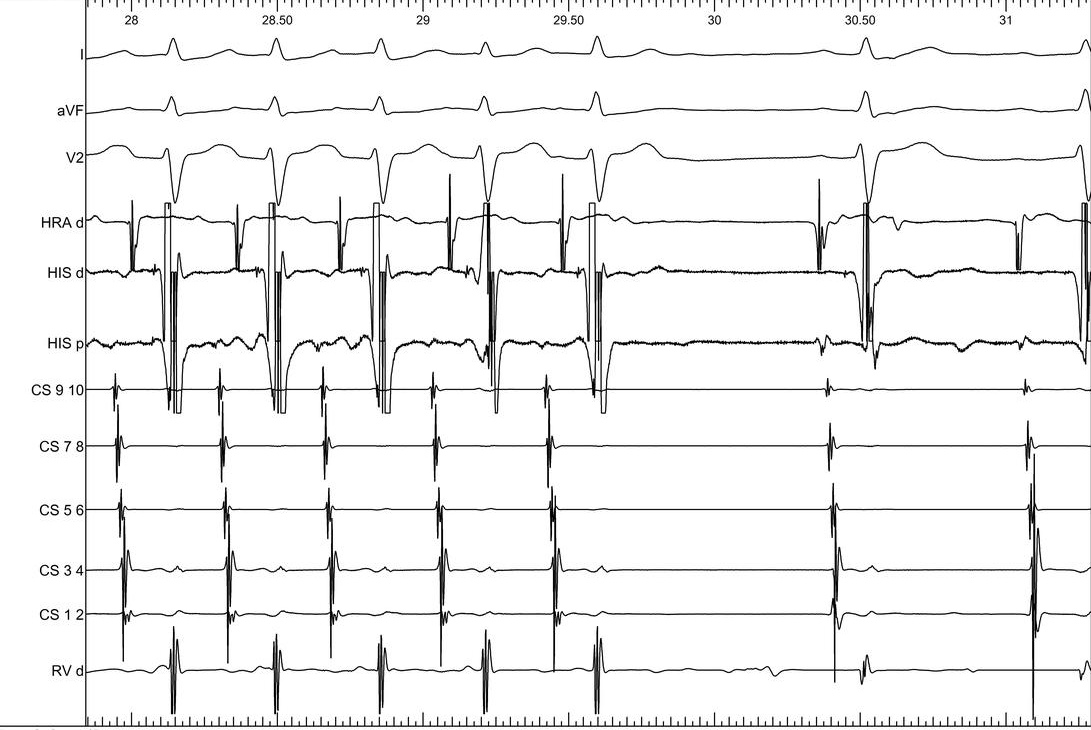

Burst atrial pacing

09_va_unlinking.jpg